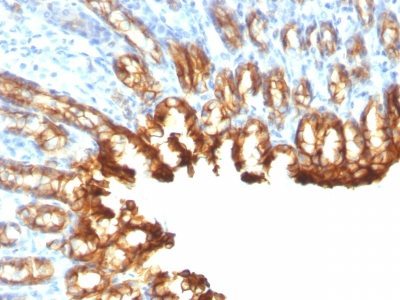

Recognizes a protein of 40 kDa, identified as cytokeratin-19 (CK19), which is expressed in sweat gland, mammary gland ductal and secretory cells, bile ducts, gastrointestinal tract, bladder urothelium, oral epithelia, esophagus, and ectocervical epithelium. Anti-CK19 reacts with a wide variety of epithelial malignancies including adenocarcinomas of the colon, stomach, pancreas, biliary tract, liver, and breast. Perhaps the most useful application is the identification of thyroid carcinoma of the papillary type, although 50%-60% of follicular carcinomas are also labeled. Anti-CK19 is a useful marker for detection of tumor cells in lymph nodes, peripheral blood, bone marrow and breast cancer.